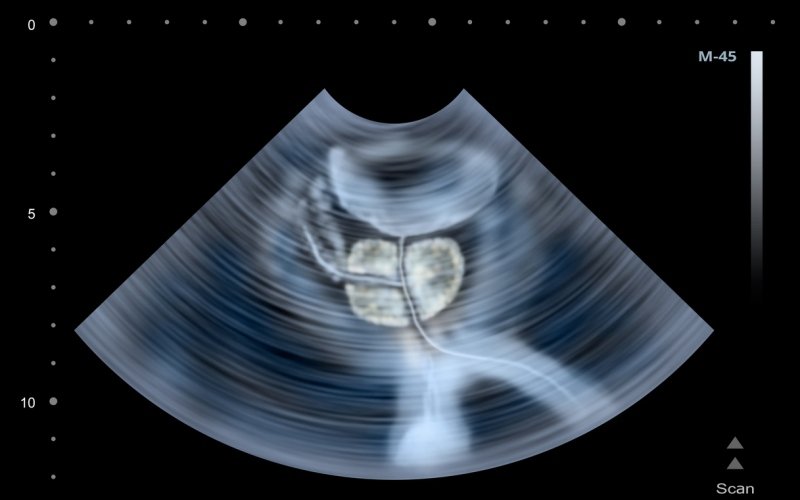

Biopsia por fusión: un mejor diagnóstico del cáncer de próstata

Te explicamos la técnica que combina la resonancia magnética y la ecografía para lograr una detección más precisa del tumor prostático

La biopsia por fusión es una de las técnicas innovadoras más eficaces para detectar el cáncer de próstata. La combinación de resonancia magnética y ecografía no solo facilita el momento de la exploración de la próstata, también consigue cen...

Avances en la detección del cáncer de próstata

La combinación de resonancia magnética y ecografía mejora la detección de tumores de riesgo

Uno de los cánceres más diagnosticados en hombres es el cáncer de próstata. Según cifras de la Sociedad Española de Oncología Médica, se detectan cerca de 30.000 casos al año. A estos alarmantes datos se suma el hecho de que, en ocasiones, ...